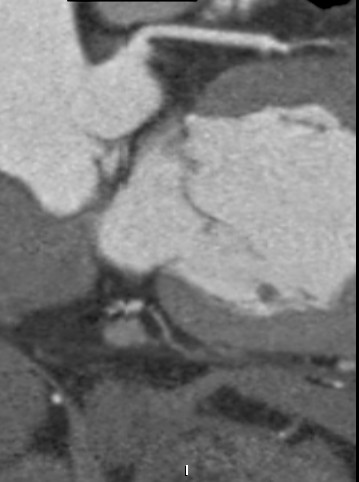

标题: CT24400:患者54岁,心前区不适进行心脏冠脉造影检查。 [打印本页]

标题: CT24400:患者54岁,心前区不适进行心脏冠脉造影检查。

患者54岁,心前区不适进行心脏冠脉造影检查。高手看看有问题没有?

图像很漂亮,好像未见异常